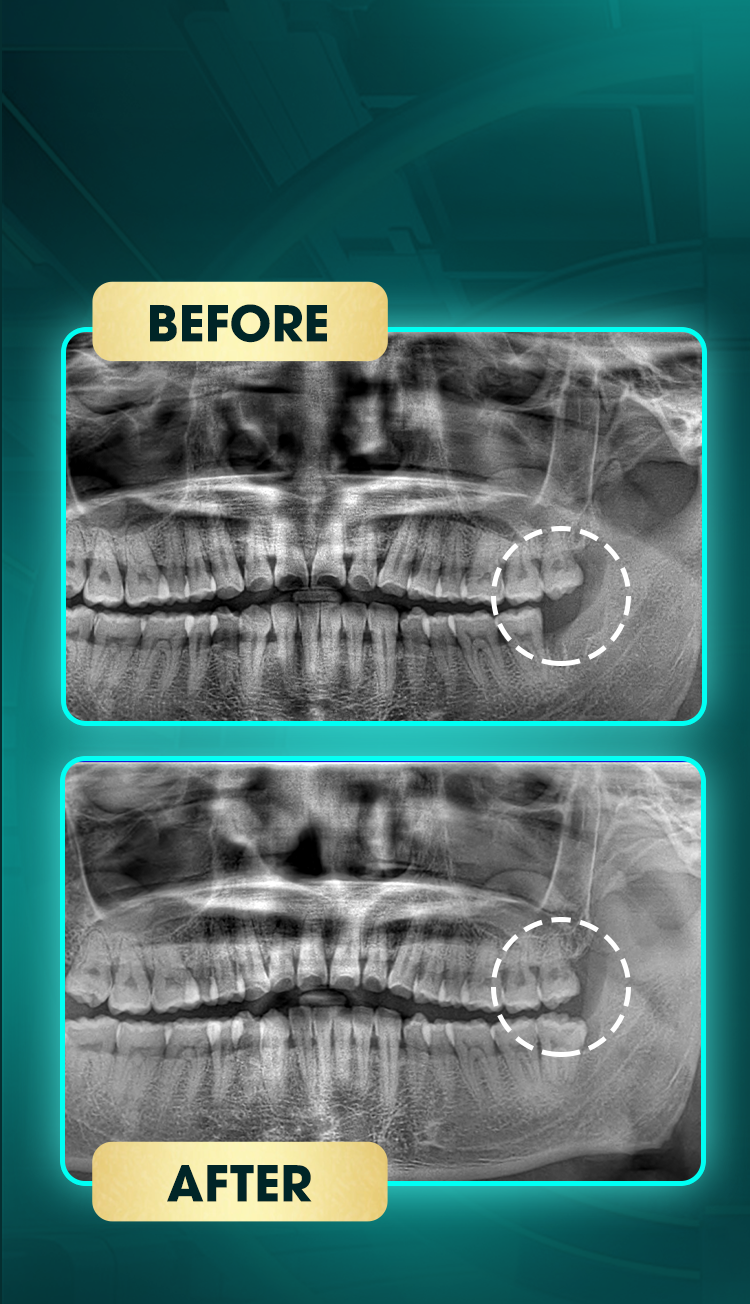

Lâm Tuấn Sơn

Tiểu phẫu răng khôn

Trước điều trị:

Răng khôn mọc lệch ngầm, chen chúc nhẹ răng hàm dưới, có dấu hiệu lệch nhẹ hàm dưới.

Sau điều trị:

Răng khôn đã được loại bỏ, không còn tình trạng chen lấn hay tác động đến răng kế cận, cấu trúc hàm ổn định.

Kết quả: